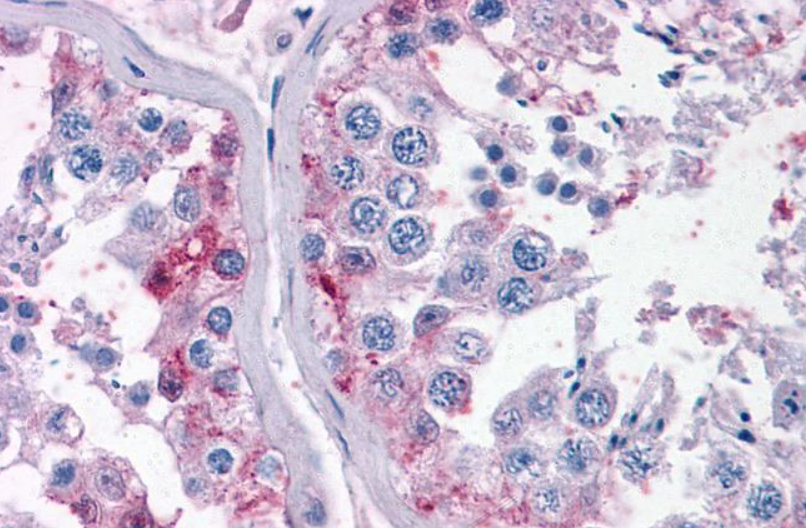

50 μl, 100 μl, 200 μlTIG2 Rabbit Polyclonal Antibody [orb11481]

IF, IHC-Fr, IHC-P

Human, Mouse, Rabbit

Human, Mouse, Rabbit, Rat

Rabbit

Polyclonal

Unconjugated

50 μl, 100 μl, 200 μlAnti-Aurora A/AURKA Antibody [orb1290027]